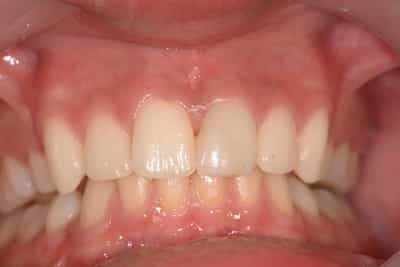

Cas numero 2 :

Situation Initiale

Etude du cas et proposition

Cas terminé